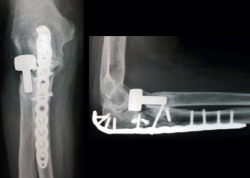

Figura 11. Reducción y fijación del cúbito con placa del olécranon y tornillo adicional, reducción y fijación de la coronoides con tornillos de la placa y 2 tornillos adicionales, y prótesis de la cabeza del radio, que se encontraba fracturada y luxada. Tras la osteosíntesis se restituyó la estabilidad en las articulaciones humerocubital y radiocubital proximal.